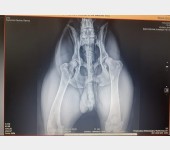

Zbieramy pieniądze na operację psa rasy Cane Corso. Wabi się RAMBO. Urodził się 1 stycznia 2018r, od jakiegoś czasu zmaga się z problemami stawów. Po zrobieniu licznych badań jedynym wyjściem okazała się operacja.. Rambo cierpi na dysplacje kości biodrowej kończyny tylnej.

Leczenie operacyjne

Potrójna osteotomia miednicy (TPO)

Operacja, której celem jest zapobieganie kalectwa.